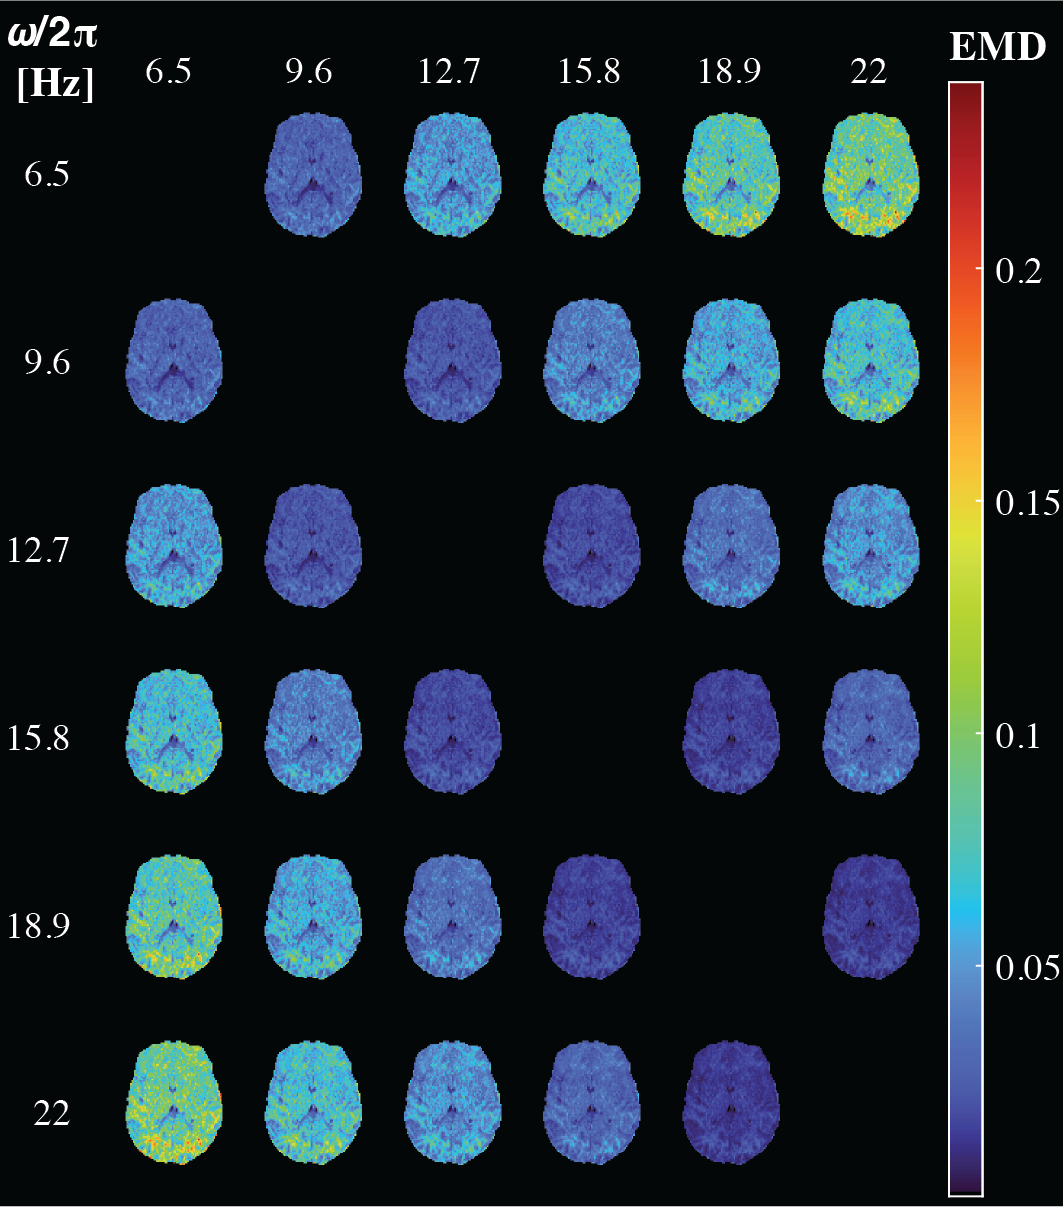

Figure 3 displays axial maps of global and bin-specific statistical descriptors of D(ω)-R1-R2 from a representative subject. The contrasts are in good agreement with previously published D-R1-R2 data.25 We observed spatial patterns of rate of frequency change of the diffusivity metrics, e.g., predominantly positive or negative values of Diso or DΔ2, respectively, in the occipital cortex. To get a more comprehensive description of the diffusion frequency dependencies in the brain, we used the earth mover’s distance (EMD)35 to quantify the voxelwise difference between 7D D(ω)-R1-R2 spectra at given diffusion frequency. Pairwise EMD values at 6 diffusion frequencies are summarized in a distance matrix, shown in Figure 4. Strongest frequency dependencies were observed in deep WM and cortical brain regions. Lastly, the ICC(3,1) and VAR values for repeatability and variability were generally high or low, respectively, for all measures (Figure 5).

Figure 4. Quantification of frequency-dependent diffusion-relaxation correlations via visualization of voxelwise pairwise earth mover’s distance (EMD) between different frequencies. Clear spatial patterns are visible, with the strongest frequency-dependent diffusion-relaxation correlations in deep WM and cortical brain regions.